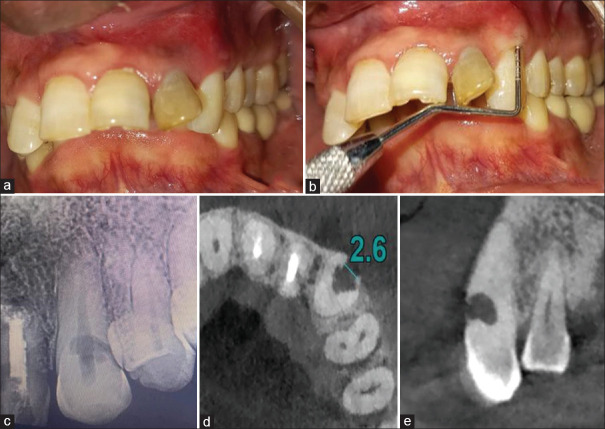

牙齿吸收;内部和外部,偶尔发生作为牙槽器感染的炎症反应。根据吸收的类型、病因和发现根吸收缺陷的阶段,提出了不同的治疗方案。本病例报告展示了通过使用生物陶瓷密封剂(BioRoot RCS)的非手术根管治疗和使用Biodentine重建吸收缺陷来治疗广泛的炎症性内外根吸收。在1、3、6和12个月的随访中,临床和影像学证据显示根尖周愈合、牙根吸收停止和牙周再植的迹象。锥束计算机断层扫描在诊断、决策和治疗计划中起着至关重要的作用,从而成功地管理这些有牙髓-牙周受累的病例。在12个月的随访中,临床和放射学结果支持,使用生物陶瓷材料可以成功地治疗广泛的牙根吸收和牙周组织累及的病例。

Tooth resorption; both internal and external, occasionally occurs as an inflammatory response of the dentoalveolar apparatus to infection. Depending on the type of resorption, etiology, and the stage at which root resorption defect is detected, different treatment regimens have been proposed. This case report demonstrates the management of extensive inflammatory combined internal and external root resorption by nonsurgical endodontic therapy using a Bioceramic sealer (BioRoot RCS) and surgical reconstruction of resorptive defect using Biodentine. On follow-up at 1, 3, 6, and 12 months, clinical and radiographic evidence revealed signs of periapical healing, arrested root resorption, and periodontal reattachment. The inclusion of cone beam computed tomography plays a crucial role in diagnosis, decision-making, and treatment planning and thus successful management of such cases having Endodontic-Periodontal involvement. As supported by clinical and radiographic findings at 12-month follow-up, treatment of cases with extensive root resorption and associated involvement of periodontium can be successfully done using bioceramic materials.